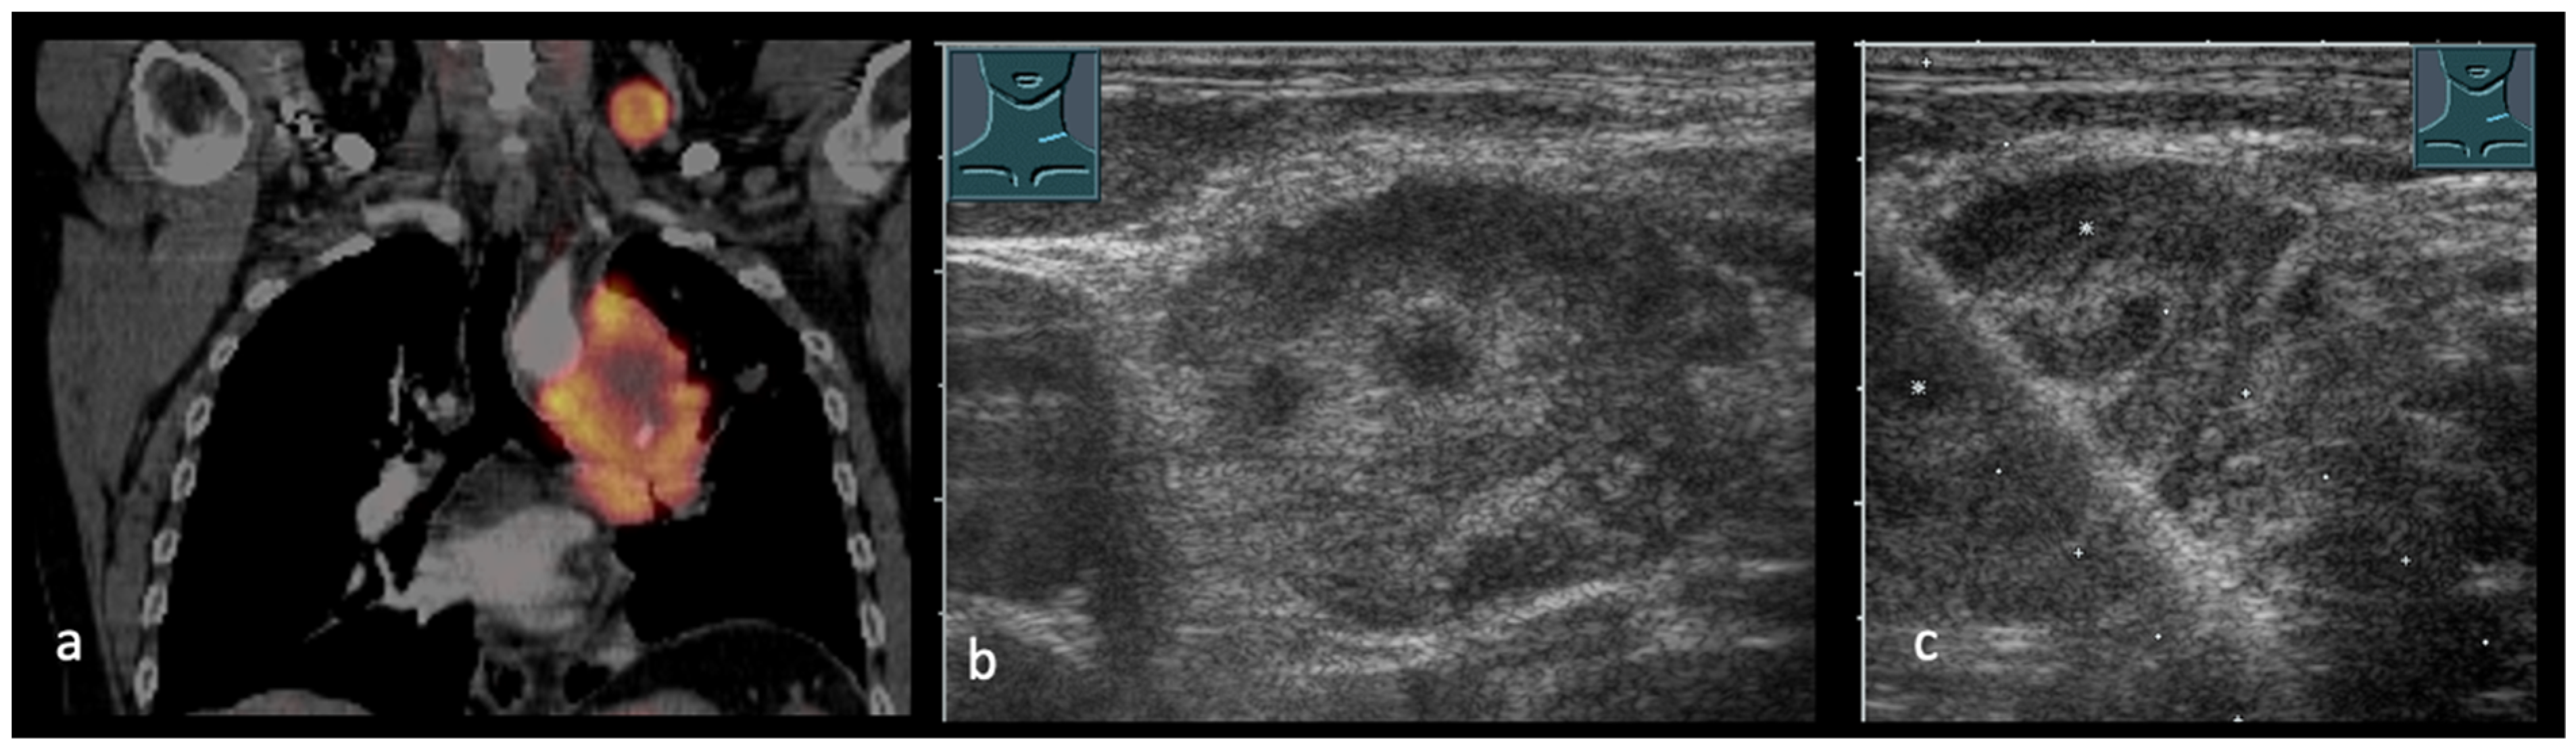

2. Transcutaneous Ultrasound in the Primary Staging of Lung Cancer

4. Transcutaneous Ultrasound in the Evaluation of Supraclavicular and Collar Lymph Nodes

5. Transcutaneous Ultrasound in the Evaluation Distant Metastasis